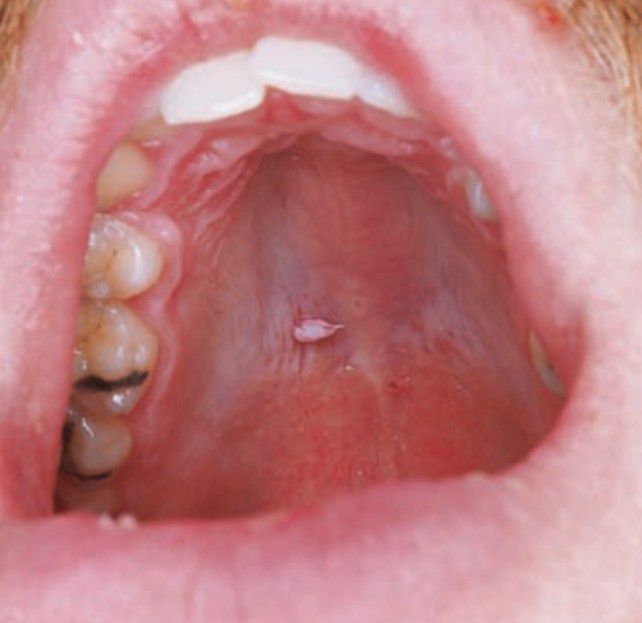

Oral wart

Oral squamous papilloma (including those of the vermilion portion of the lip) is the most common papillary lesion of the oral mucosa and accounts for approximately 2.5% of all oral lesions.